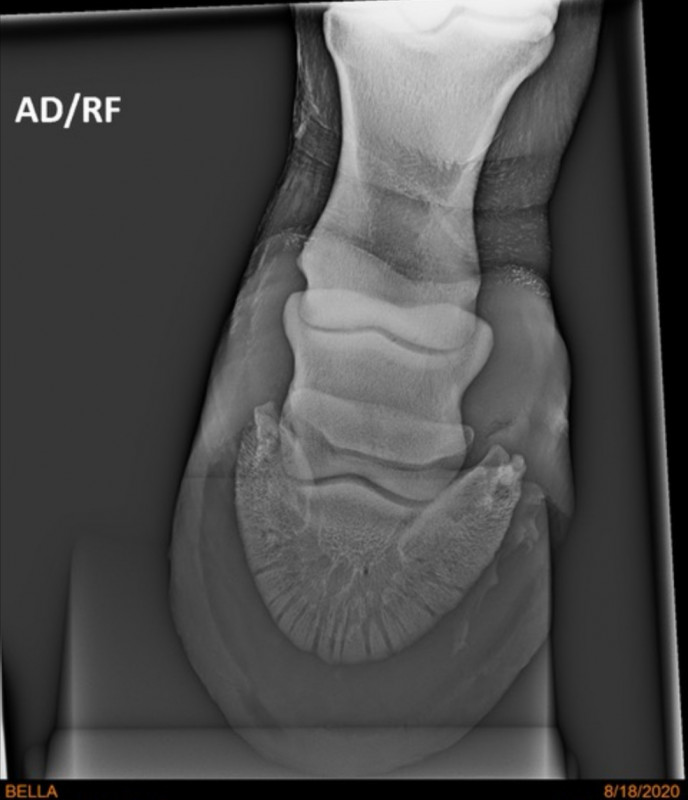

Je poste les radios qui avaient été faites quand même. La veto n'avait rien vu mais au cas où...